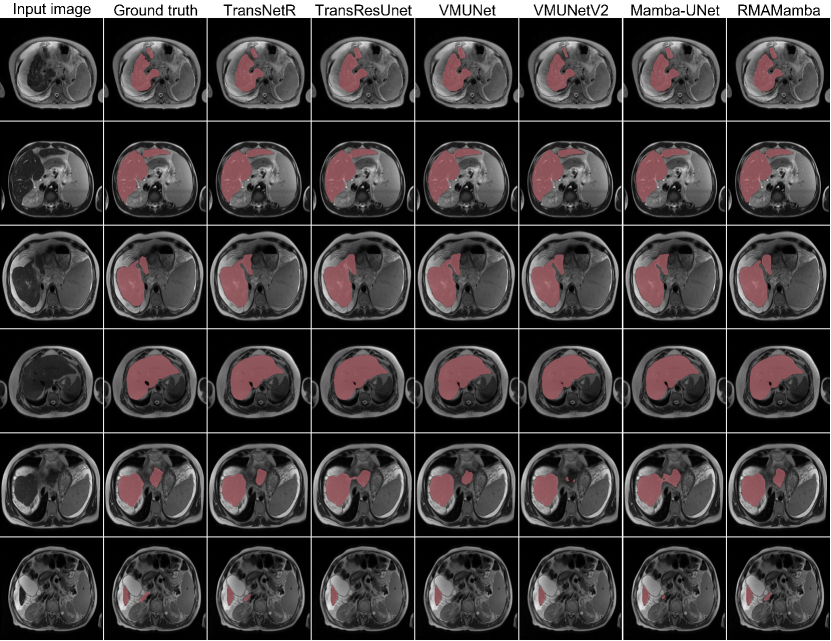

Refer to caption

Figure 2: Qualitative results of different methods on the CirrMRI600+ dataset.

Our extensive experimentation on the pathological liver segmentation benchmark dataset demonstrates RMA-Mamba’s superior performance (Table 1). RMA-Mamba-T outperforms existing CNN and Transformer-based architectures while showing marked improvement over recent SSM-based approaches like VM-UNet and Mamba-UNet. The larger variant, RMAMamba-S, achieves state-of-the-art performance with a Dice score of 92.08%, mIoU of 87.36%, and Hausdorff Distance of 3.39 mm.

While Transformer-based methods (TransResUnet: 92.58%, PVTFormer: 92.48%) and CNN-based approaches (Double-UNet: 92.37%) demonstrate competitive performance, they incur substantial computational overhead and longer training times. RMA-Mamba achieves comparable or superior results while maintaining computational efficiency and faster training convergence. Qualitative analysis (Figure 2) further validates our method’s effectiveness, particularly in challenging cases. The visualization results, especially evident in rows three and five, demonstrate RMA-Mamba’s superior boundary delineation and enhanced discriminative capability at tissue interfaces.